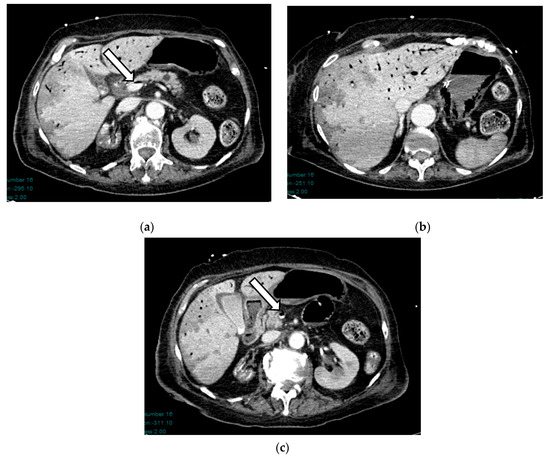

Acute mesenteric ischemia (AMI) is a clinical condition caused by vascular insufficiency, resulting in intestinal damage. Is often underestimated, if not driven by clinical suspicion, due to the non-specific clinical symptoms (usually represented by acute abdominal pain) and the absence of reliable markers, which results in a poor prognosis and high mortality. We can identify three main forms of AMI: arterial, venous, and non-occlusive. Arterial AMI is the most frequent form, caused by occlusion of the superior mesenteric artery or one of its branches. Venous AMI is the least frequent, caused by thrombosis of the superior mesenteric vein or its branches. Non-occlusive AMI is due to a state of hypovolemia, which is frequent in patients who have undergone surgery. Given the difficulty of diagnosis based on the clinic alone, the radiologist plays a central role in identifying radiological signs of intestinal ischemia and in avoiding misdiagnosis. The radiologist’s role is mainly to identify factors predictive of necrosis, which allow us to stratify patients and direct them towards the proper management. The aim of this review is to provide indications for an adequate CT protocol, including an unenhanced phase, an arterial phase, and a venous phase, as well as to underline the features to investigate in the different forms of AMI, in order to increase the diagnostic capacity in this challenging disease. Full article

Figure 1